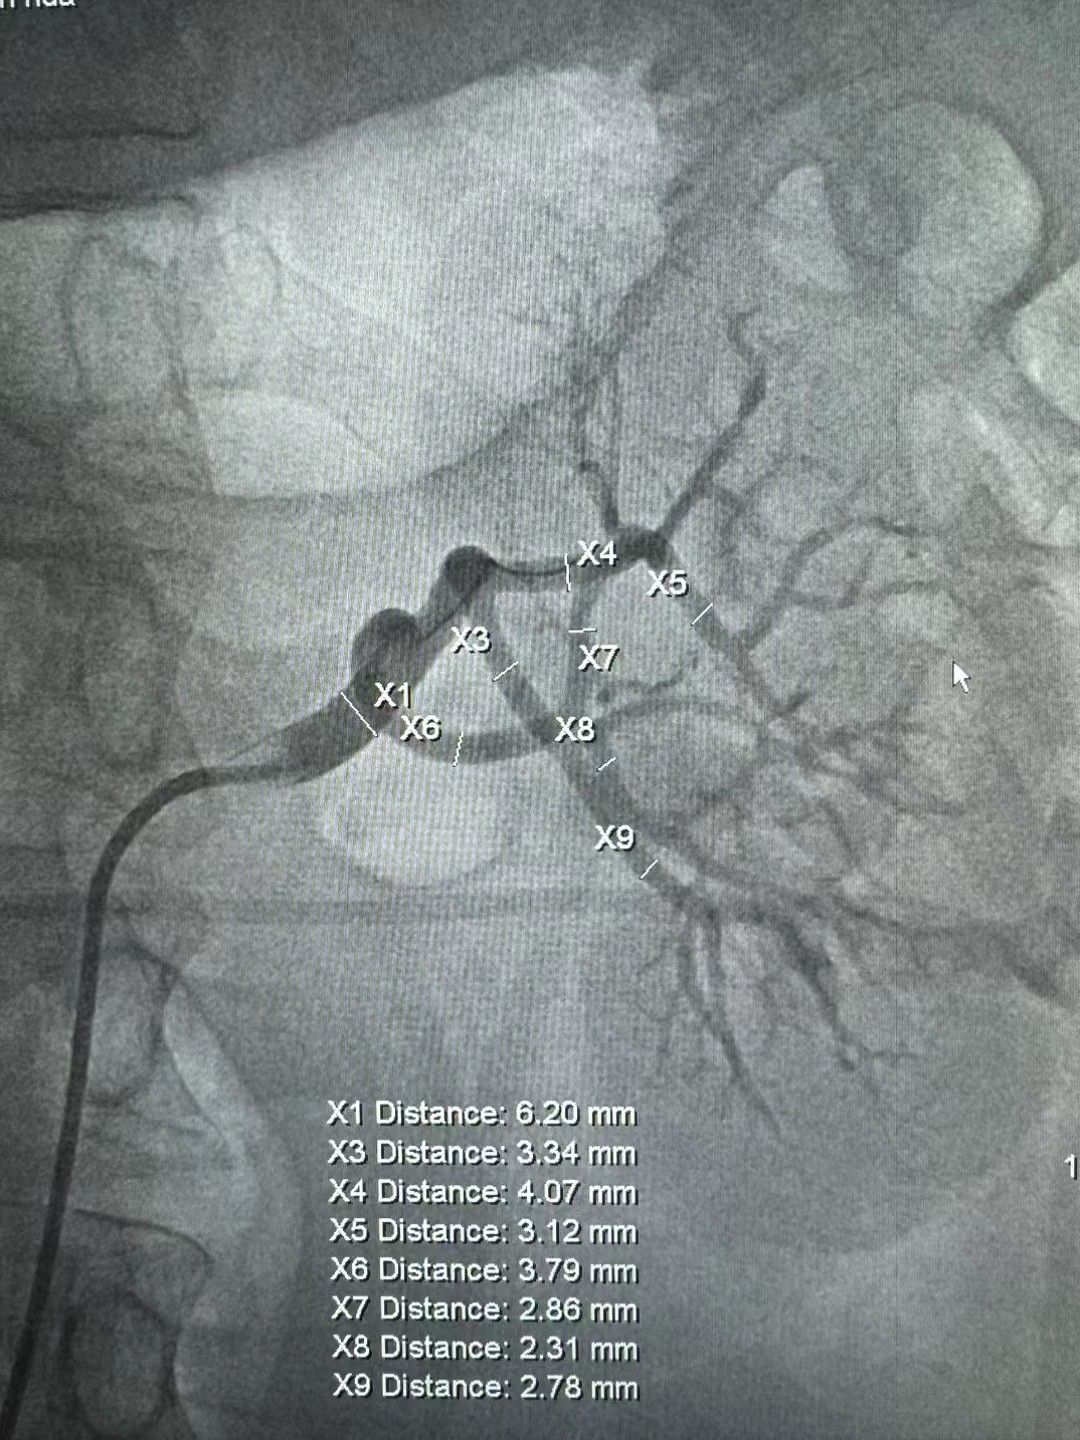

我中心现配有 20 余台医用智能化电子血压计,可实时传输血压数据;20余台 24 小时动态血压监测仪,具备多导心电图,动态心电图,动态血压监测,超声心动图,颈动脉超声多普勒,脉搏波传导速度,无创心功能检测,踝臂血压指数,尿微量蛋白,尿白蛋白定量,眼底检查,计算机断层扫描血管造影,心脏磁共振和动脉造影等检查设备条件和技术。此外,我院于2023年通过港澳药械通项目引入经皮肾动脉交感神经消融术(RDN)的微创手术,成为国内大陆地区首家批准开展RDN的医疗机构。同时开展的肾上腺静脉取血术以及肾动脉狭窄支架植入术等在继发性高血压诊治领域也取得良好效果。

肾动脉狭窄支架术